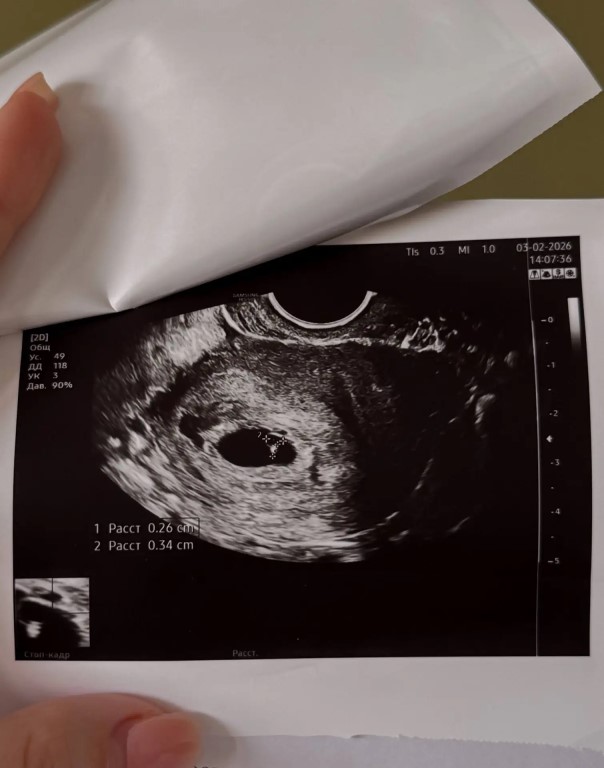

Фото В общем, через пару дней я залетела в кабинет к гинекологу со словами «у меня потрясающие новости!!» на что она мне ответила «вы беременны!!», видимо для них это обычная практика)) Она решила сделать еще раз узи и уже у нее было сердцебиение🥹 тут у меня весь мир перед ногами перевернулся, я услышала сердечко малютки♥️ Господи, наконец-то я вам рассказала, вы не представляете, как мне каждый день хотелось с вами поделиться!! И вот я сообщаю вам спустя 14 недель, пройдя уже кучу испытаний и первый скрининг и мне еще столько всего нужно вам рассказать, девочки🥹🥹🥹